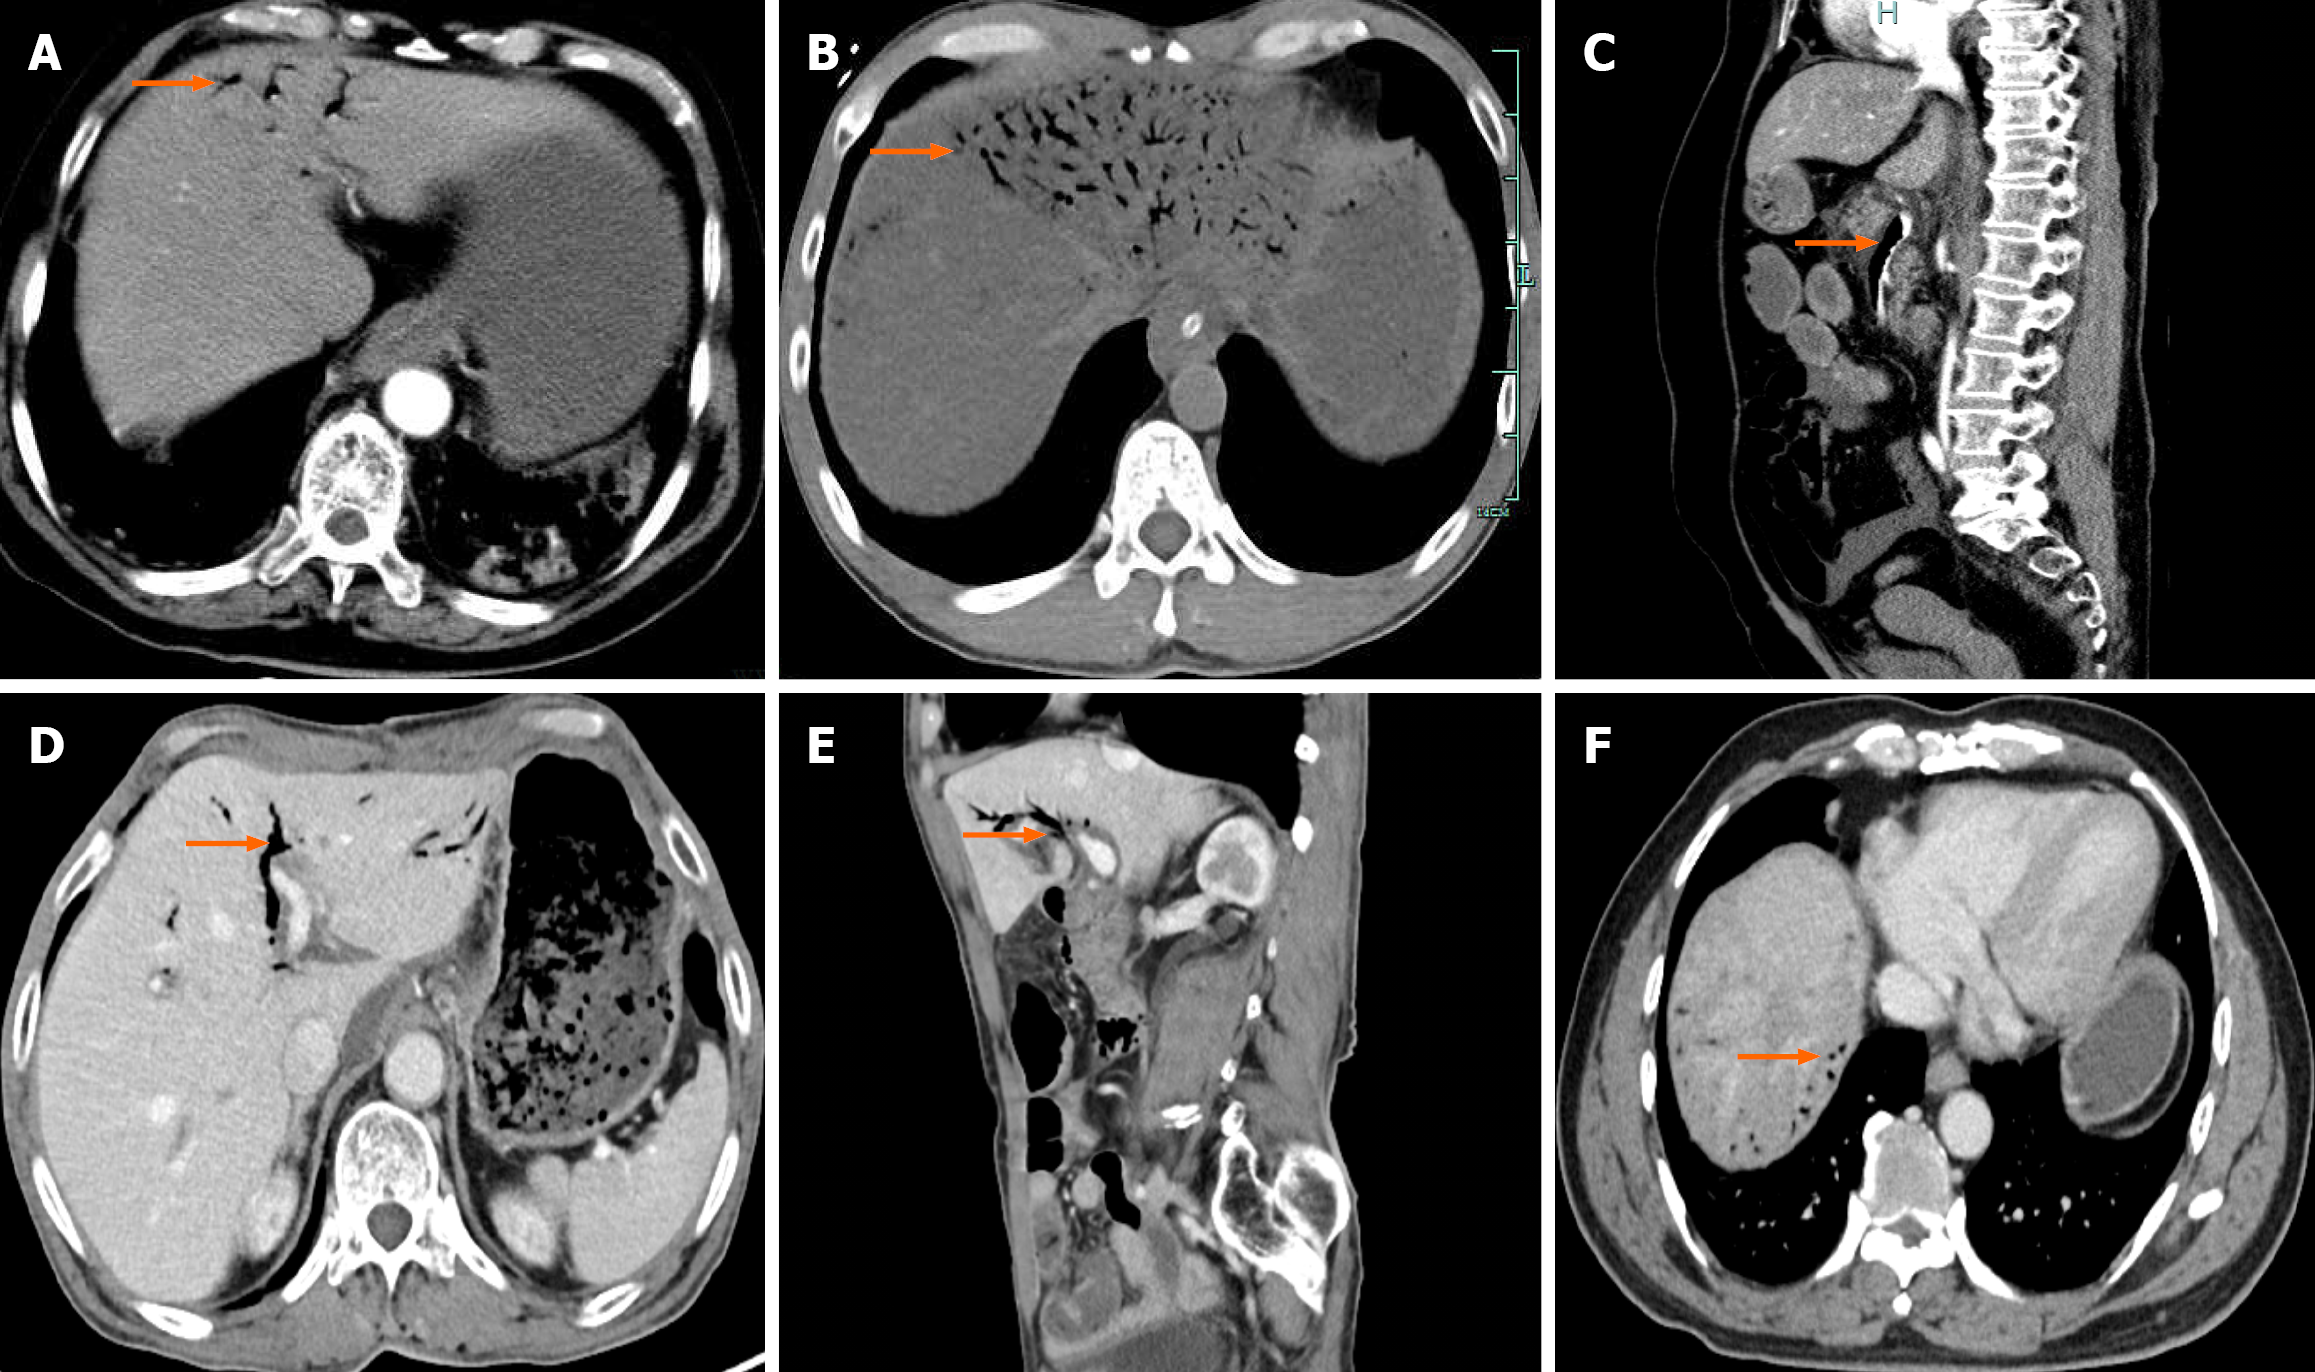

At early stage, the detection of HPVG primarily relied on X-ray imaging, which typically revealed characteristic bran